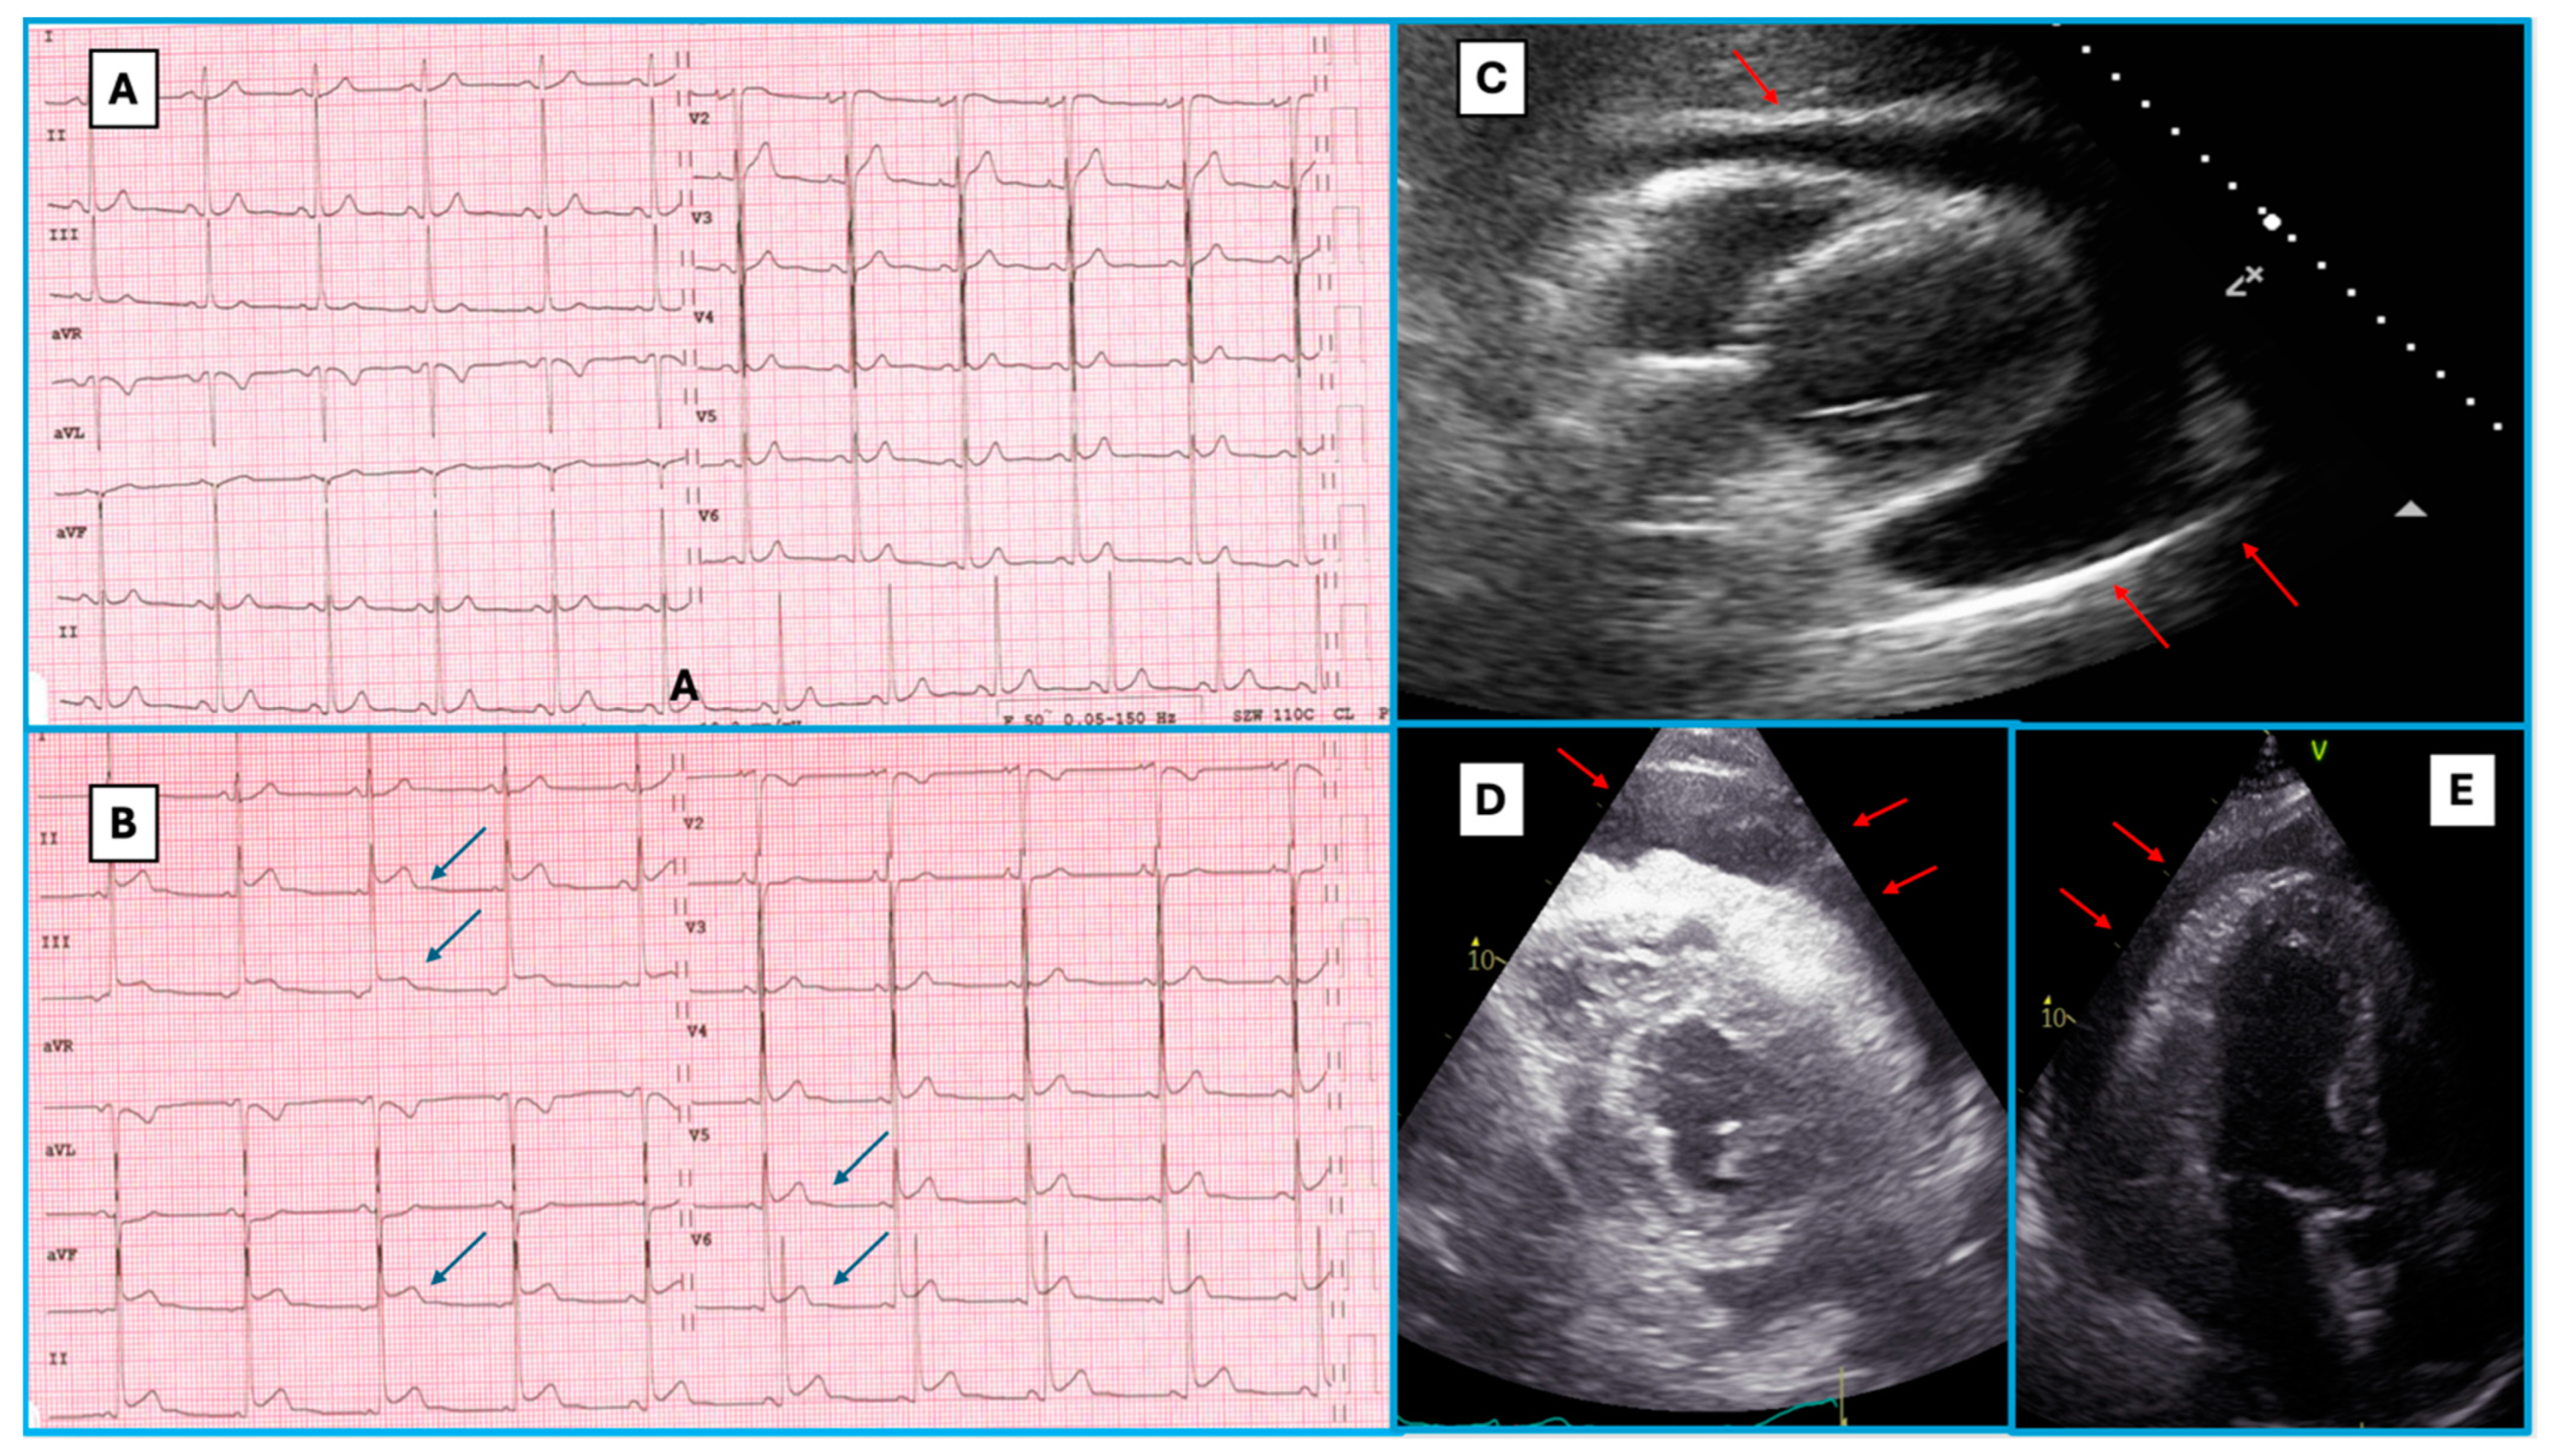

3.4. Constrictive Pericarditis Cases